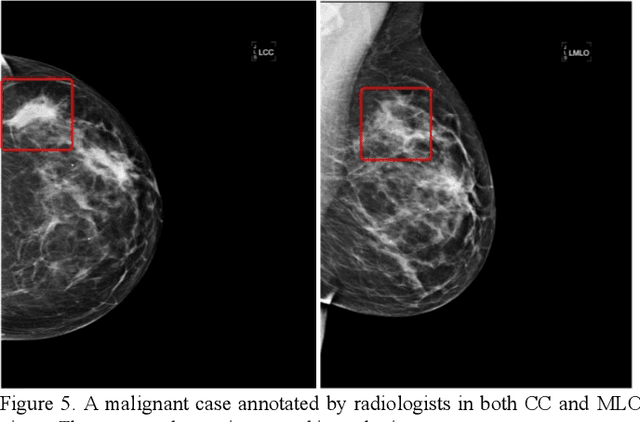

Abstract:Machine learning is widely used in developing computer-aided diagnosis (CAD) schemes of medical images. However, CAD usually computes large number of image features from the targeted regions, which creates a challenge of how to identify a small and optimal feature vector to build robust machine learning models. In this study, we investigate feasibility of applying a random projection algorithm to build an optimal feature vector from the initially CAD-generated large feature pool and improve performance of machine learning model. We assemble a retrospective dataset involving 1,487 cases of mammograms in which 644 cases have confirmed malignant mass lesions and 843 have benign lesions. A CAD scheme is first applied to segment mass regions and initially compute 181 features. Then, support vector machine (SVM) models embedded with several feature dimensionality reduction methods are built to predict likelihood of lesions being malignant. All SVM models are trained and tested using a leave-one-case-out cross-validation method. SVM generates a likelihood score of each segmented mass region depicting on one-view mammogram. By fusion of two scores of the same mass depicting on two-view mammograms, a case-based likelihood score is also evaluated. Comparing with the principle component analyses, nonnegative matrix factorization, and Chi-squared methods, SVM embedded with the random projection algorithm yielded a significantly higher case-based lesion classification performance with the area under ROC curve of 0.84+0.01 (p<0.02). The study demonstrates that the random project algorithm is a promising method to generate optimal feature vectors to help improve performance of machine learning models of medical images.